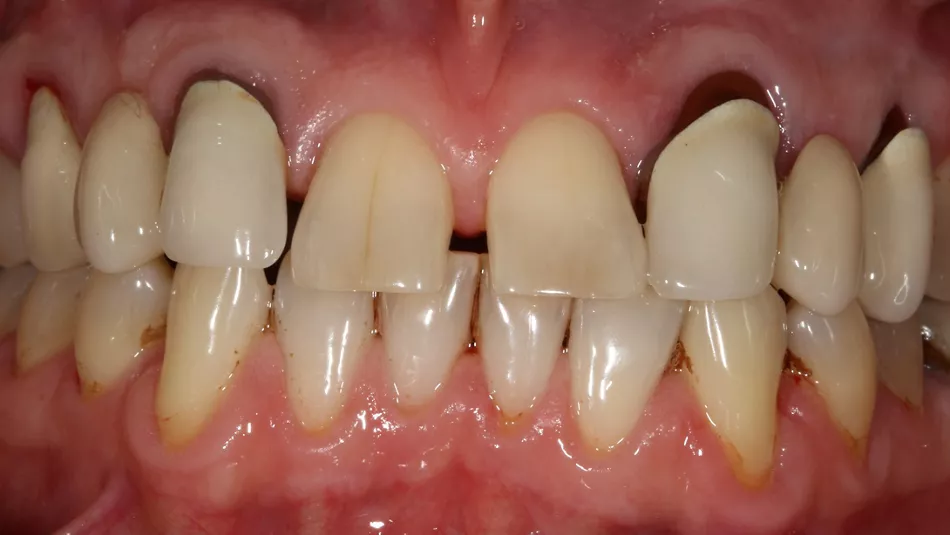

This 65-year-old patient was a non-smoker in good health. He presented with good periodontal status and a low (or maintained low) smile line. Many restorations had been carried out over time, without affecting occlusal function. There was a natural diastema between teeth 11 and 21. There were also two bridges, created to offset agenesis of the maxillary lateral incisors.

1. The two mesially tipped upper canines and first premolars supported two bridges that had been remade 3 times. Repeated decementation in the upper left quadrant and an infection in 2018 made the patient decide to agree to the proposed implant treatment.